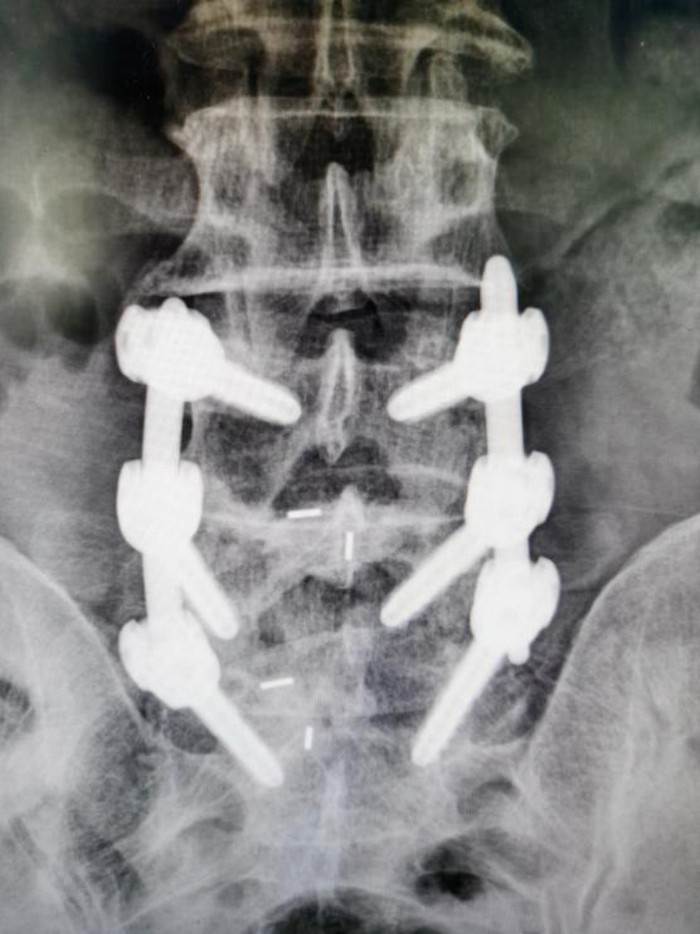

术后腰椎X-ray片提示:内固定位置满意/图源 重医附三院